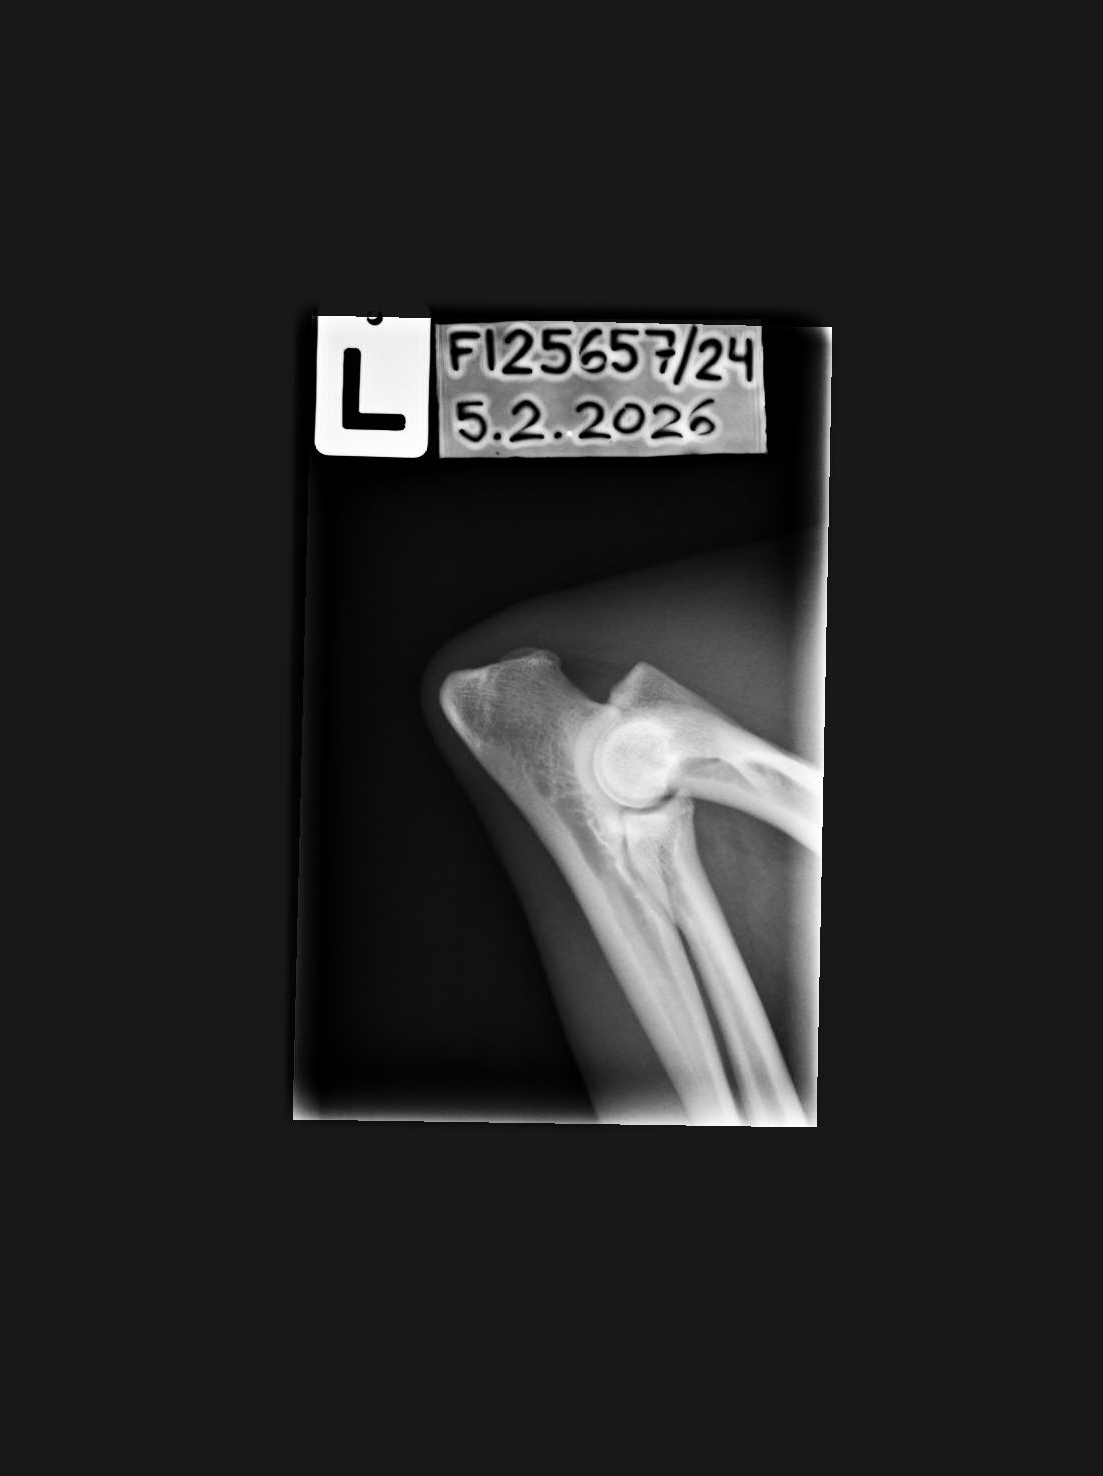

0/0 |